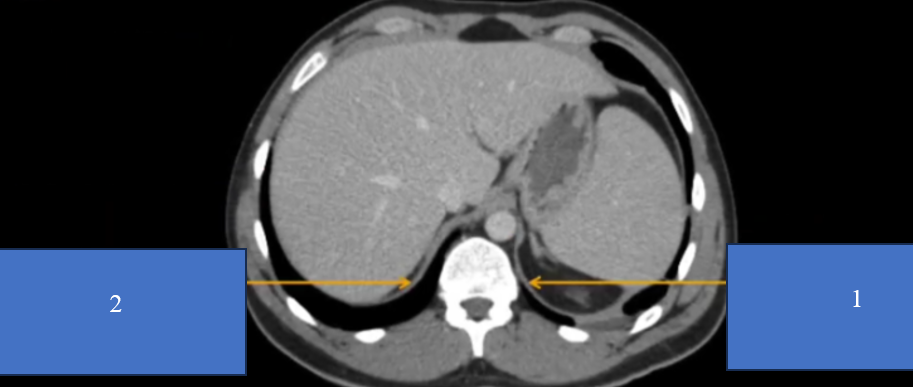

TM gan ở đâu? TM chủ dưới ? ĐM chủ?